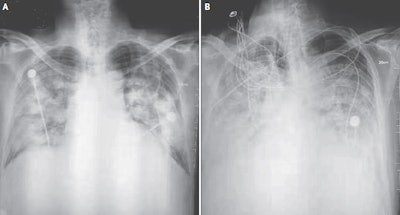

Each of the patients presented with a combination of fever, cough, and chest discomfort. The patients underwent chest x-ray and CT exams that showed pneumonia-like findings, which the researchers referred to as "novel coronavirus-infected pneumonia." The radiographs of the one patient who died showed an increase in density, profusion, and confluence of bilateral opacities over time, in addition to the accumulation of pleural fluid.